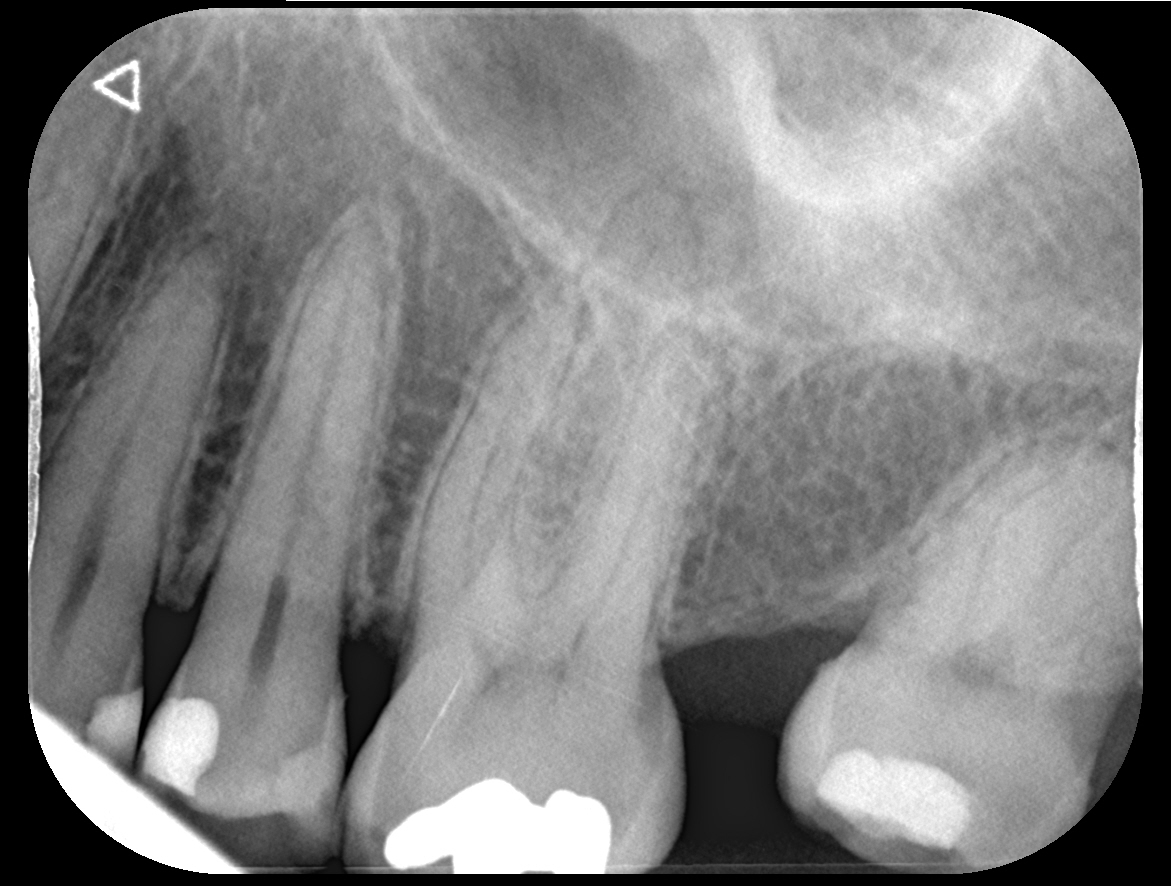

Uiteindelijk was ik in het buitenland en kreeg ik weer last. Uiteindelijk cbtc scans gedaan en microscopisch 4 kanalen. Was heftig lang. Geen verticale fracturen gevonden maar wel gevuld met glasvezel stiften. Dame werkte bij alldent in Frankfurt. Kroon vond ze met huidige stand niet nodig maar goed. Even je objectieve mening wat vindt je er van?. Ze was extreem secuur. Napijn wel met bijten maar was vanwege grote behandeling gebruikelijk. Kan nog even zeuren. Laesie was minimaal volgens haar.

Ja die indruk kreeg ik ook. Nu inderdaad afwachten. Was is hier nu meestal het proces wanneer je zegt afwachten. Ontsteking moet minder worden etc? Op de foto vond ze die minimaal maar de pulpa was al langer afgestorven. Dat afwachten is het heel proces?

ziet er netjes uit...nu…

over een jaar controle x=foto